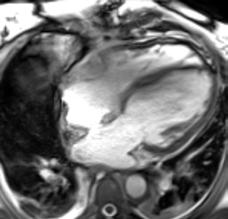

In contrast to acute complications, chronic complications are generally more unique to the Caesarean section itself, and are not typically seen with other surgical procedures, with the exception of incisional hernia. Caesarean scar niche was identified as an important cause of pain and irregular bleeding (Figure 1).

Figure 1: Caesarean scar niche.

C-section: Caesarean section; US: ultrasound.

Acute complications included injury to adjacent organs, bleeding, and haemorrhage, along with the risks associated with anaesthesia, typical of acute complications seen with most surgical procedures. The organs most at risk during a Caesarean section are the bladder, ureters, and bowel, due to their proximity to the uterus. Most of the postoperative collections observed were located anterior to the uterus in the uterovesical space, or wound infections in the subcutaneous tissue.

The complications identified in this local review of Caesarean section cases align with the recognised complications documented in the literature.

The purpose of this pictorial review is to depict the various complications associated with Caesarean sections, and their appearances on different imaging modalities using local cases.

While Caesarean sections are generally considered safe, there are a range of associated complications. With the increasing frequency of Caesarean sections, a corresponding rise in the incidence of complications can be expected. Therefore, it is important to ensure that radiologists can effectively identify the most common complications and their features across different imaging modalities.